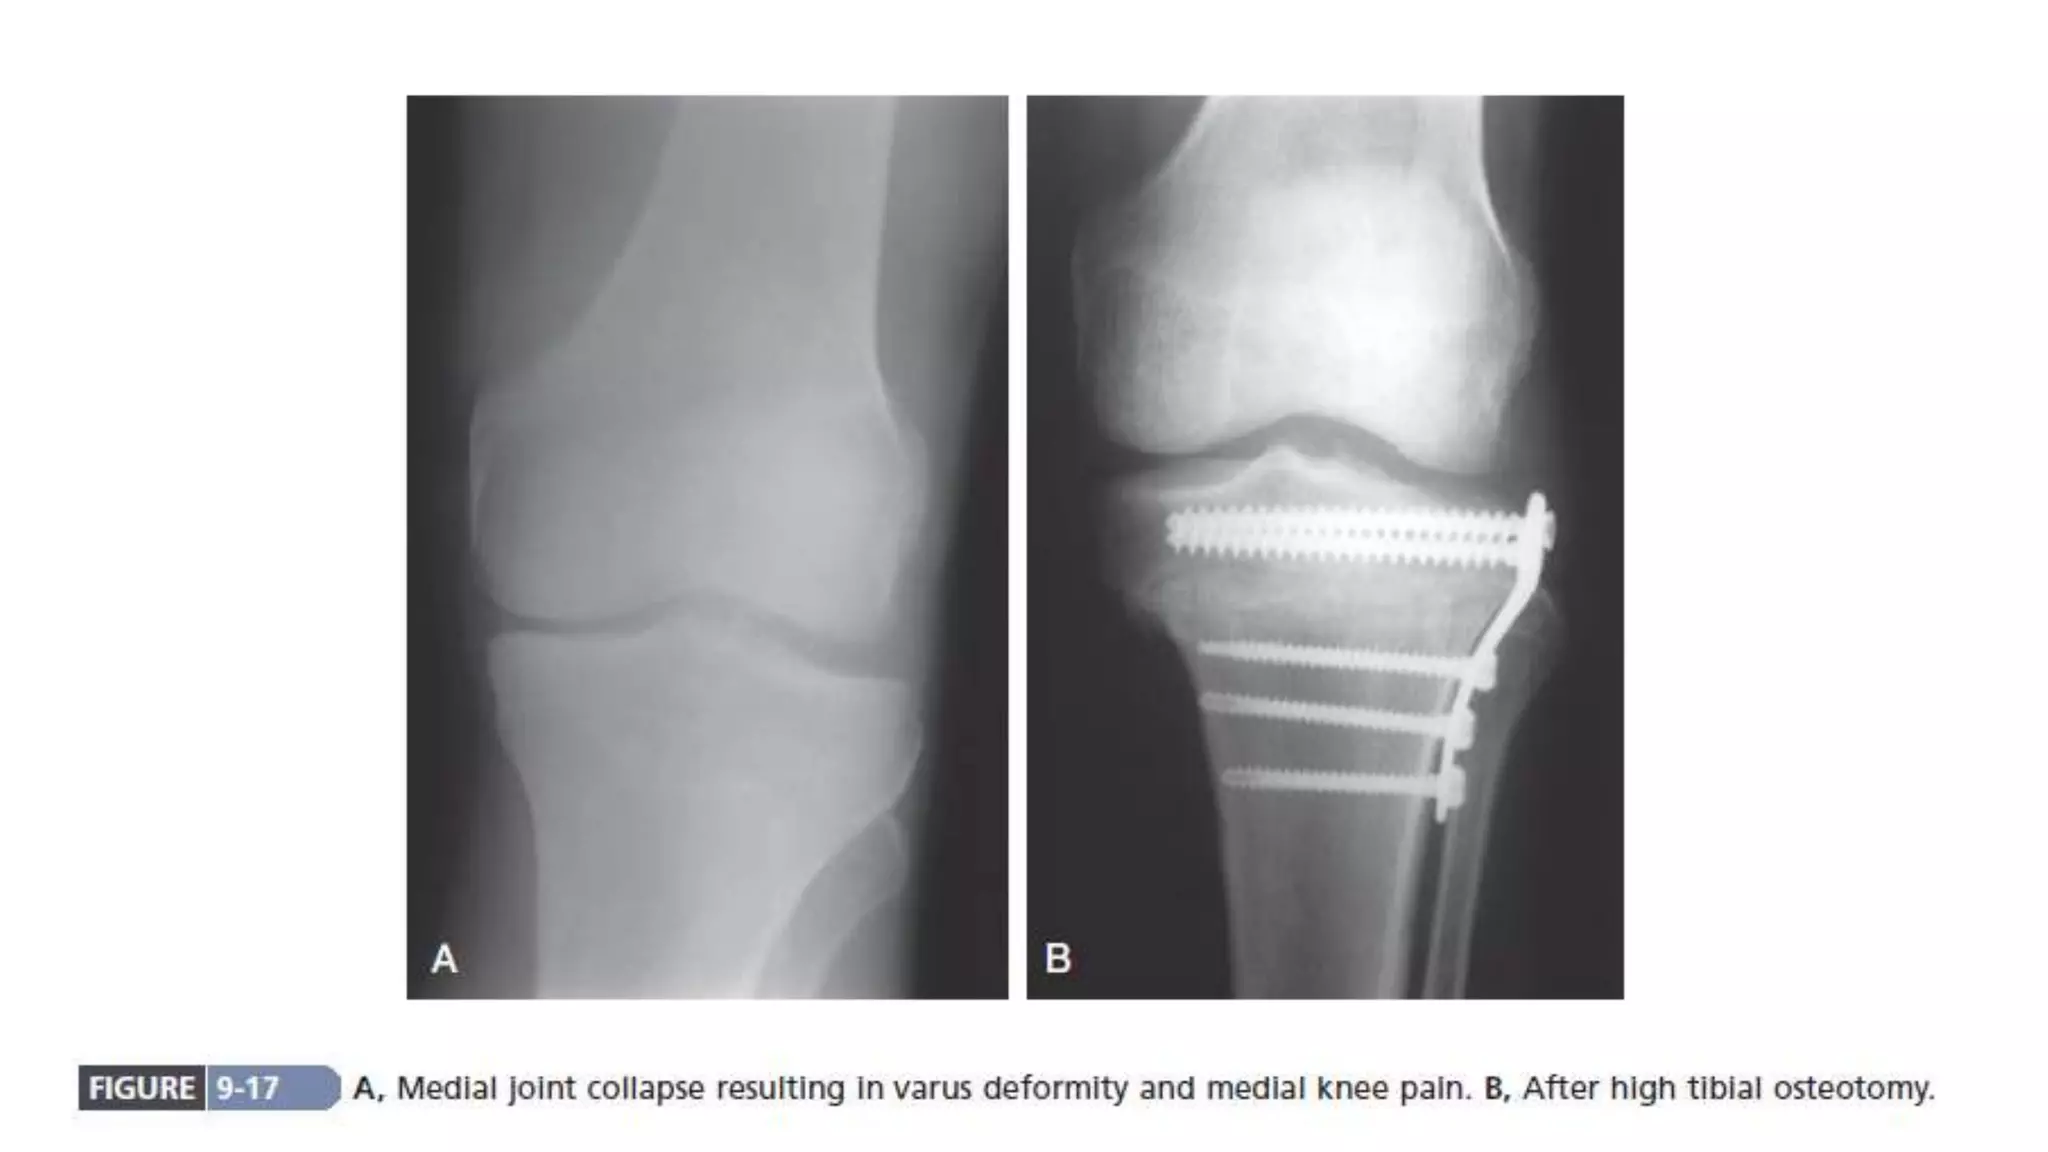

Progressive joint destruction, with increasing pain,

Realignment osteotomy (joint with deformities like high tibial

osteotomy for OA knee). Major part of articular cartilage is

still preserved. Dramatic pain relief.

Vascular decompression of subchondral bone

Redistribution of load towards less damaged part of the joint

Progressive joint destruction,with increasing pain, instability and deformity usually requires reconstructive surgery Realignment osteotomy (joint with deformities like high tibial osteotomy for OA knee). Major part of articular cartilage is still preserved. Dramatic pain relief. Vascular decompression of subchondral bone Redistribution of load towards less damaged part of the joint Operative Modalities